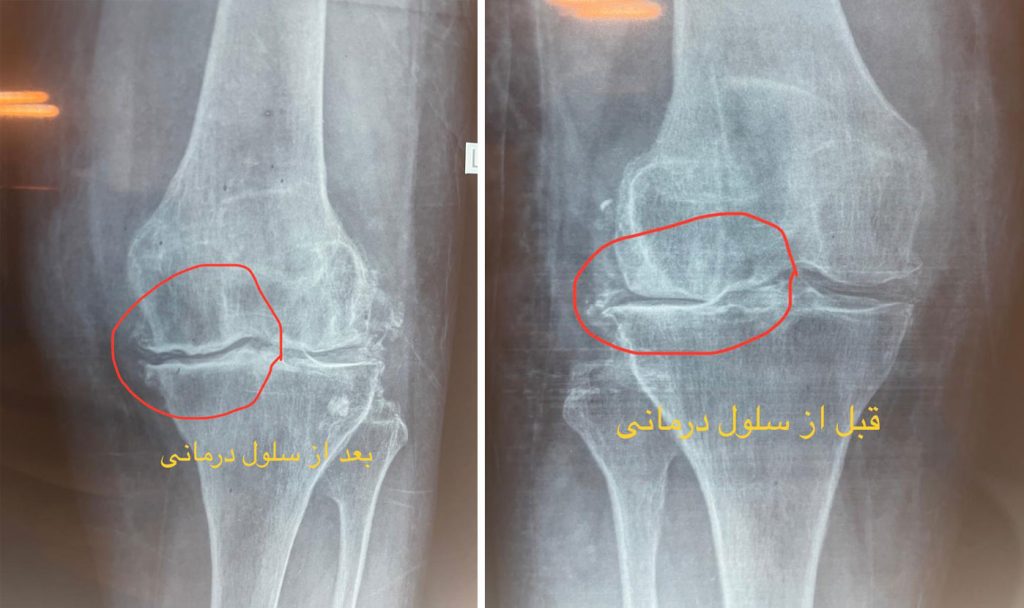

سلول درمانی زانو قبل و بعد

چندین مطالعه و کارآزمایی بالینی نشان داده اند که تزریق داخل مفصلی سلول های بنیادی مزانشیمال می تواند در بهبود عملکرد و کاهش درد در بیماران مبتلا به آرتروز زانو موثر باشد. برخی نتایج شامل بهبود نمرات درد، افزایش محدوده حرکتی مفصل و بازسازی قسمتی از غضروف آسیب دیده بوده است.